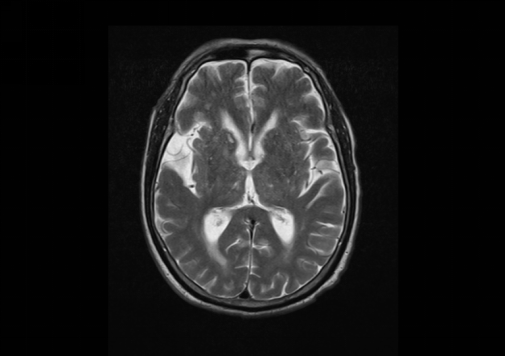

術前檢查提示多發(fā)缺血灶、腔梗灶

陳大爺今年80歲了,經(jīng)檢查發(fā)現(xiàn),他右側頸內(nèi)動脈起始部重度狹窄,狹窄達80%-90%,并且頸動脈分叉部內(nèi)膜增生及斑塊形成,右側基底節(jié)及頂葉多發(fā)腦梗死病灶!由于狹窄后造成血流減少,已經(jīng)嚴重影響到大腦供血。神經(jīng)內(nèi)科醫(yī)療團隊討論了陳大爺?shù)牟∏?,認為患者的病情嚴重,隨時有發(fā)生腦梗死的可能,需要緊急實施手術治療,遂請神經(jīng)外科會診。